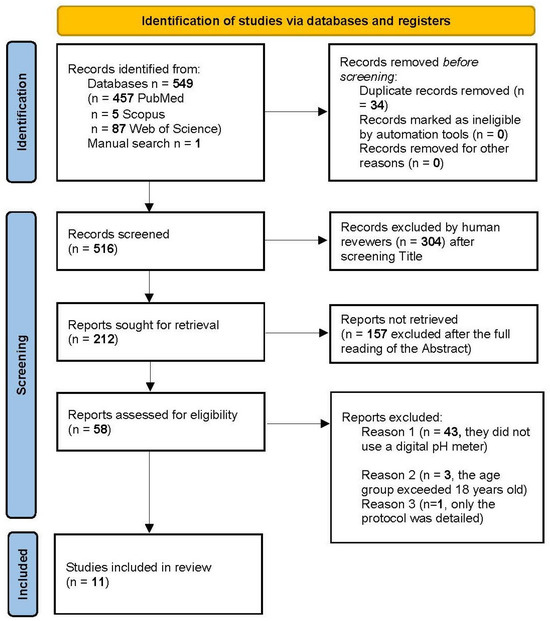

英文标题:The Integration of Salivary pH Meters and Artificial Intelligence in the Early Diagnosis and Management of Dental Caries in Pediatric Dentistry: A Scoping Review

中文标题:唾液pH计与人工智能聯合應用于兒童齲病早期診療:範圍綜述

文章链接:https://www.mdpi.com/2673-6373/5/1/12